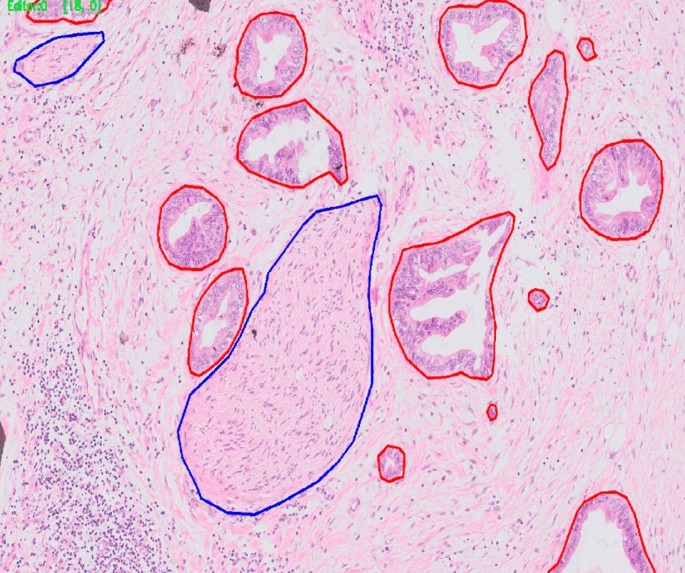

The results obtained were still not sufficient for clinical application because false alarm rates were too high and detection rates were not high enough. Analysis of the results showed multiple reasons for false alarms. For example, a significant fraction of the false alarm in tumor identification was due to misclassification of benign glands as tumor (Fig. 4). As the clinical application of the algorithm will be based on both identification of PNI elements (nerve and tumor) and their close spatial association, we thought that misclassification of benign glands as tumor would not impair the algorithm’s function. This is because benign glands do not appear in very close proximity to nerves.

The research included a training step, an analytical performance analysis step, and a clinical performance analysis step. Data from the images included direct annotation of tumor and nerves (Fig. 6) as well as the remainder of the image designated as negative-labeled background.